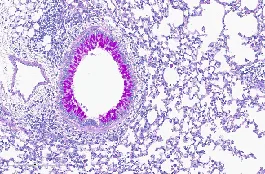

01.H&E染色